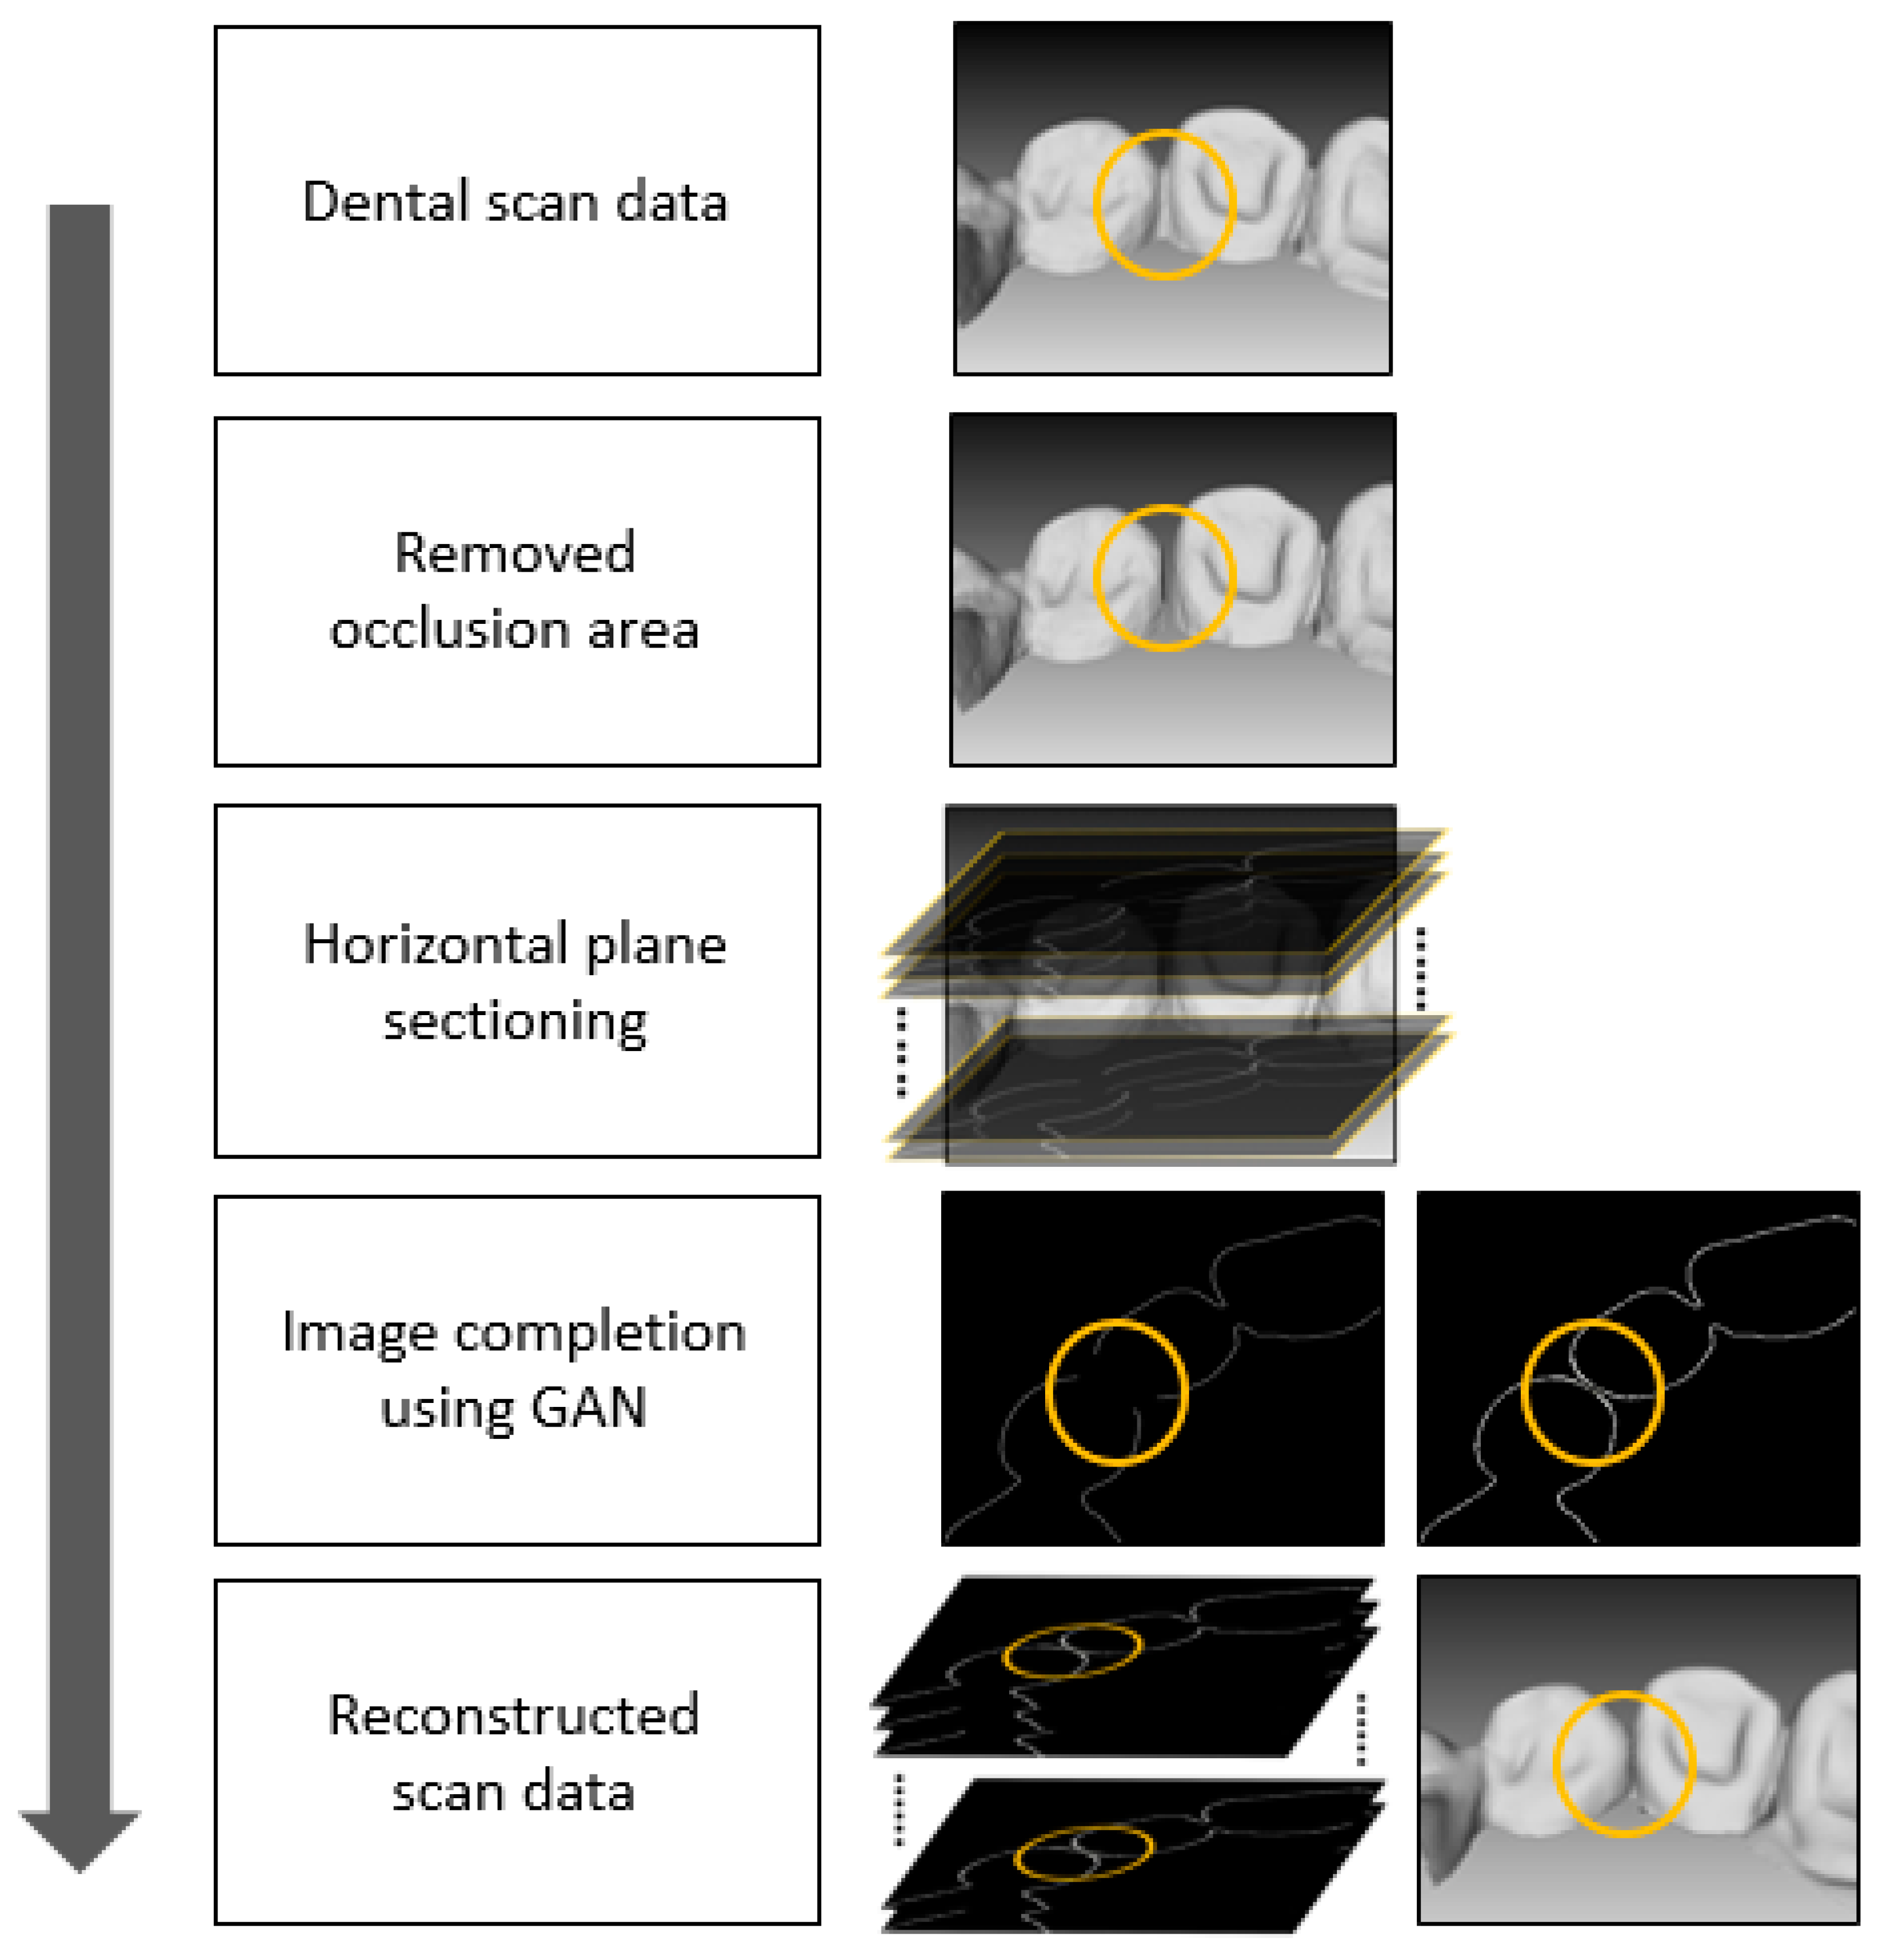

2. Proposed Method

2.1. Overview

2.2. Reconstruction of Dental Scan Data

2.3. Training GAN

2.3.1. Data Preparation

2.3.2. Training Steps